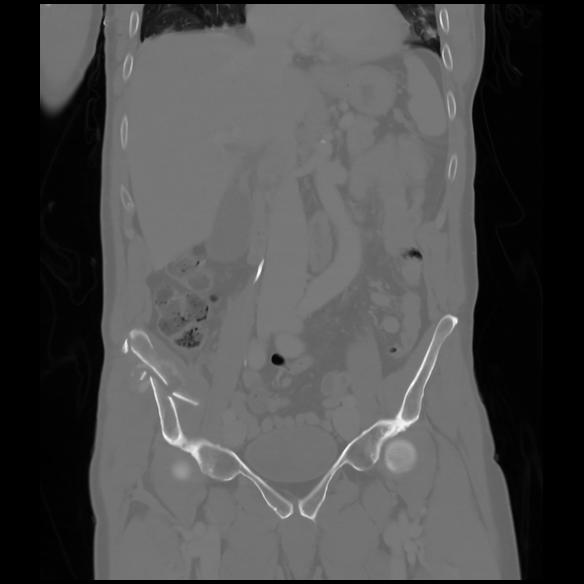

6 CUERPO,CE,Coronal,3.000,CUERPO,Coronal,